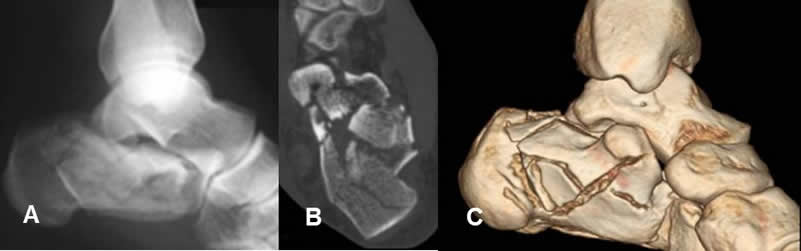

Fig 41. Fractura conminuta.

A: Rx lateral: Fractura conminuta e impactada del calcáneo.

B: TAC axial y C: TAC reconstrucción 3D: Múltiples fragmentos óseos, por estallido del calcaneo.